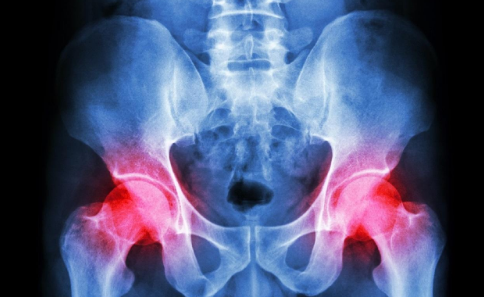

說到骨癌,相信大家應(yīng)該都不會(huì)感到陌生了,骨癌的發(fā)病率越來越高,嚴(yán)重威脅著每個(gè)人的身心健康,并且對(duì)于骨癌患者朋友們來說,治療骨癌也需要用很長的時(shí)間,目前來說,骨癌應(yīng)該如何治療呢?